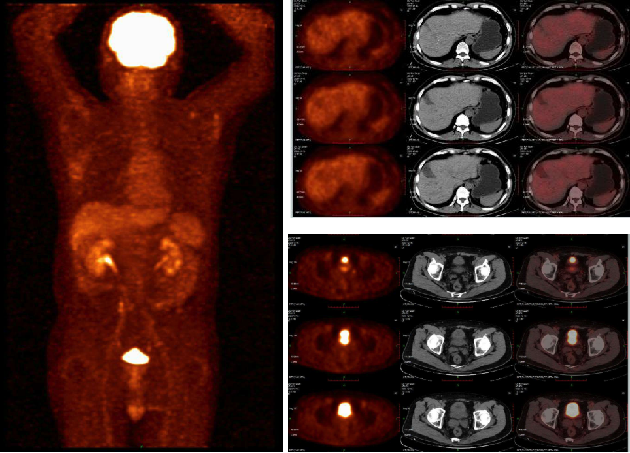

(4)2020-4-30 PET-CT:直肠前壁明显增厚,突出于肠壁呈团块状占位,FDG代谢显著异常活跃,部分坏死,考虑恶性肿瘤;盆腔中份、左侧盆壁及直肠左侧见淋巴结显影,FDG代谢异常活跃,考虑直肠肿瘤淋巴结转移。

2020-12-16 18 F-FDG PET/CT提示:直肠壁未见确切异常增厚及糖代谢异常增高,盆腹部淋巴结未见增大及糖代谢异常增高;肝囊肿。